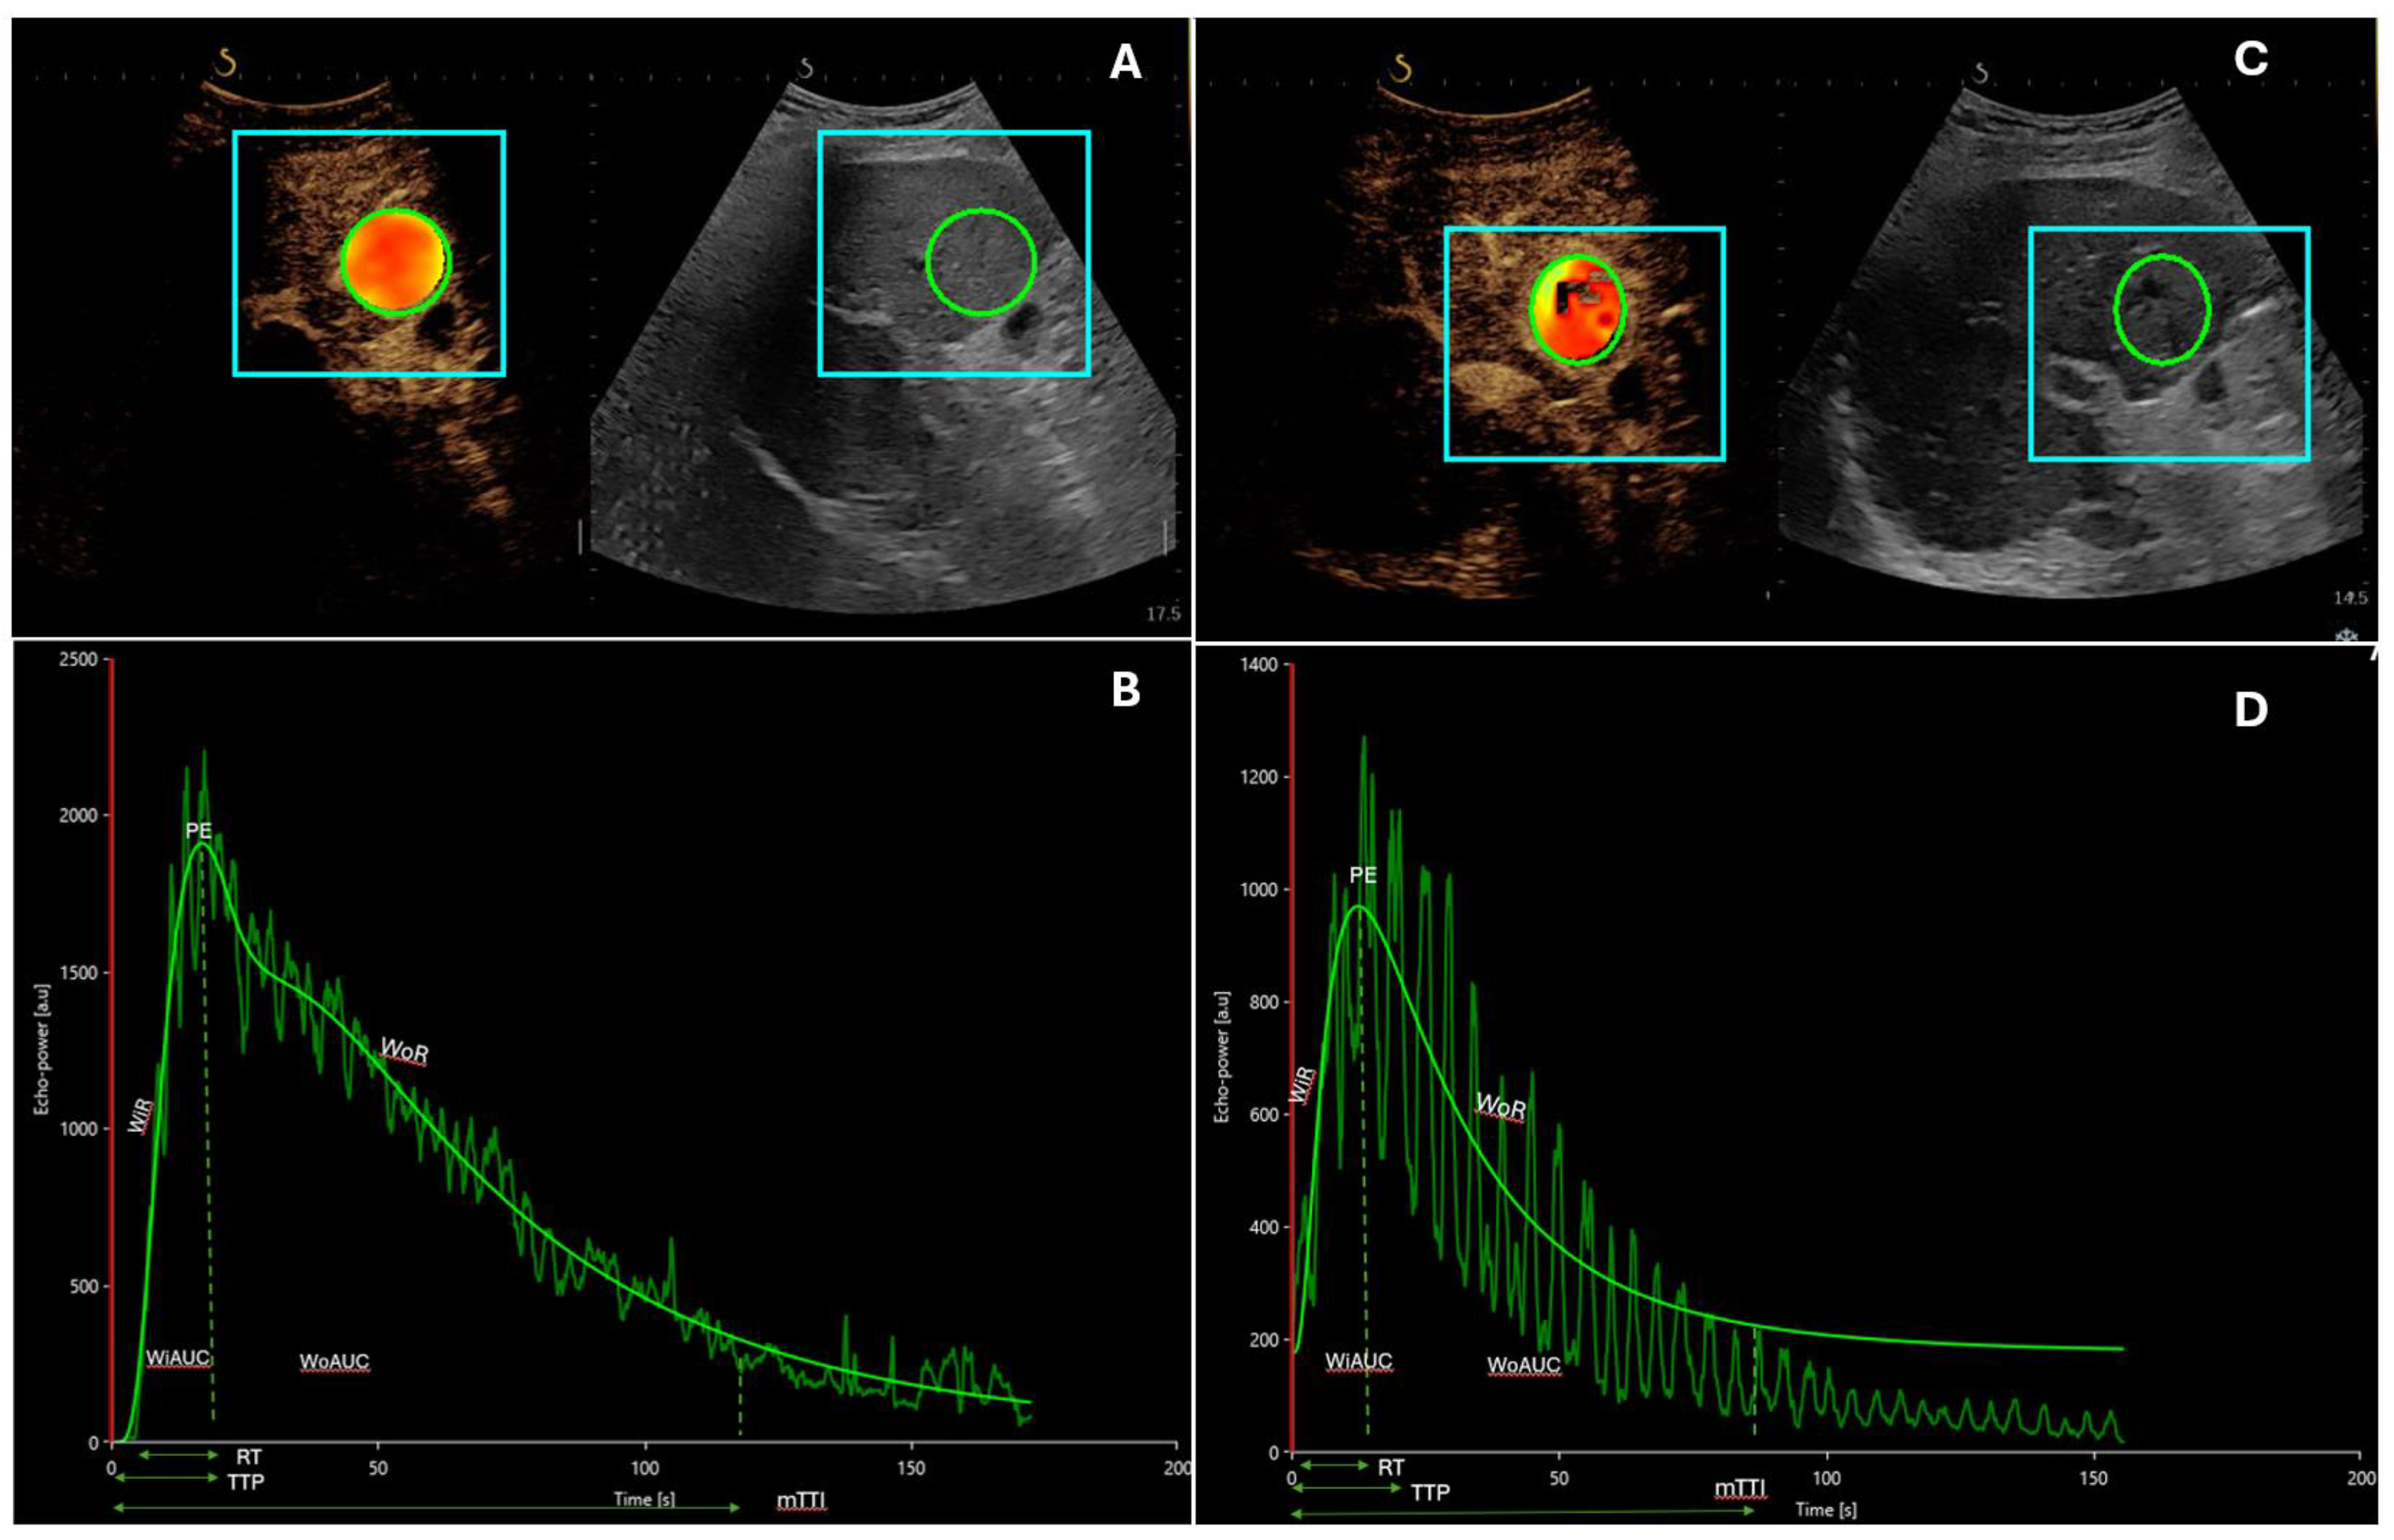

- Zocco, M.A.; Garcovich, M.; Lupascu, A.; Di Stasio, E.; Roccarina, D.; Annicchiarico, B.E.; Riccardi, L.; Ainora, M.E.; Ponziani, F.; Caracciolo, G.; et al. Early Prediction of Response to Sorafenib in Patients with Advanced Hepatocellular Carcinoma: The Role of Dynamic Contrast Enhanced Ultrasound. J. Hepatol. 2013, 59, 1014–1021. [Google Scholar] [CrossRef] [PubMed]

| Zocco [34] | 28 | SonoVue®, Bracco, Italy | Sorafenib | Mean overall survival (OS): responders > non-responders (382 versus 158 days; p = 0.003) Decrease at 15 and 30 days: peak-intensity (PI; p < 0.001), time to PI (Pw; p = 0.003), area under the curve (AUC; p = 0.002) Correlation between performance free survival (PFS), Pw, Tp, AUC |